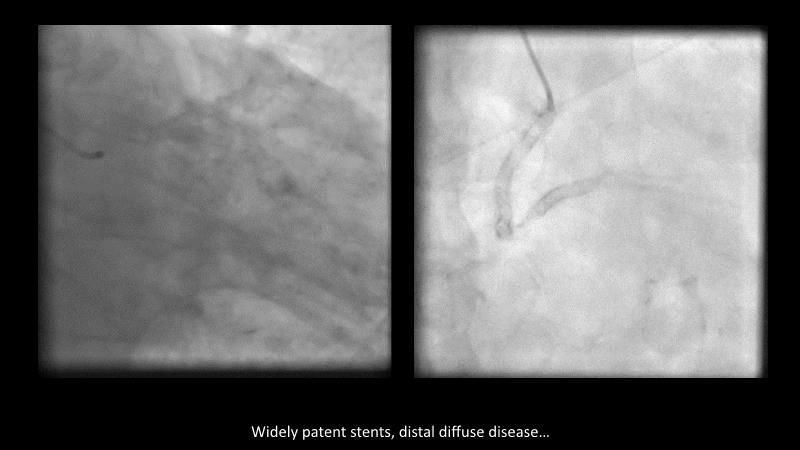

Maximize patient clinical outcomes in complex percutaneous coronary interventions (PCIs) by joining this session. Discover how accurate patient evaluation, advanced imaging/functional modalities, optimized procedures, and the Cre8 EVO device contribute to improved safety and efficacy, and review the challenges associated with DES implantation in complex PCIs.

- To review today's technical and clinical challenges of complex PCIs in complex patients related to DES implantation